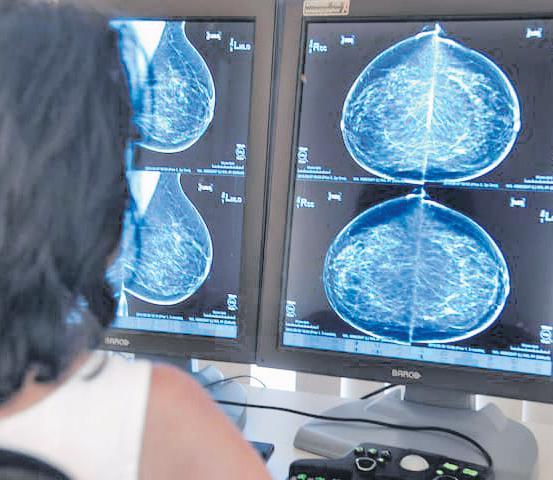

Bevolkingsonderzoek borstkanker in Meerssen

Nederland start medio april 2024 met een nieuwe onderzoeksronde van het bevolkingsonderzoek borstkanker in Meerssen. Vrouwen van 50 tot en met 75 jaar die in het postcodegebied 6231, 6235, 6237, 6241 en 6243 wonen, ontvangen een uitnodiging voor het onderzoek. Het onderzoek wordt uitgevoerd in een onderzoekscentrum op de parkeerplaats naast gemeenschapshuis De Stip aan de Pastoor Dominicus Hexstraat 10, 6231 HG Meerssen.